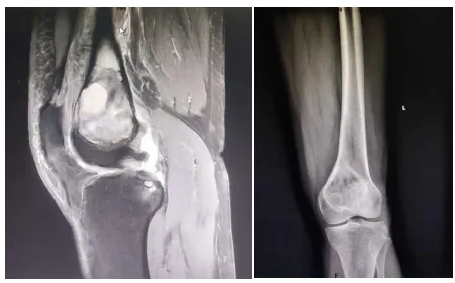

术前患者CT图。图源 重庆大学附属黔江医院